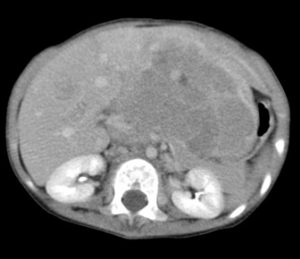

腎芽腫(じんがしゅ、Wilms腫瘍)は、小児の腎腫瘍の一つ。小児腎腫瘍の中ではもっとも頻度が高く90%を占め、全小児悪性腫瘍においても6%をしめる代表的な腹部悪性腫瘍である。ウィルムス腫瘍と呼ばれることも多い。

神経芽腫、肝芽腫と並び、小児の3大固形悪性腫瘍のひとつである。好発年齢2歳〜5歳で、3歳〜4歳でピークを迎える。後腎原基細胞に由来すると考えられている。WT1遺伝子の片側に変異が生じると腎不全と仮性半陰陽を認めるFraiser症候群をおこし、両側に変異を起こした場合に腎芽腫が発生する。発生率の男女差は、同等かやや女児に多い傾向がある。

腹部超音波検査、CT、MRIなど。